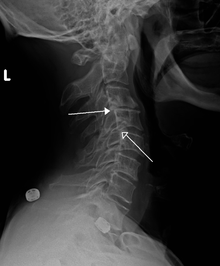

A retrolisthesis is a posterior displacement of one vertebral body with respect to the adjacent vertebrae to a degree less than a luxation (dislocation). Clinically speaking, retrolisthesis is the opposite of spondylolisthesis (anterior displacement of one vertebral body on the subjacent vertebral body), and is also called retrospondylolisthesis.[1] Retrolistheses are most easily diagnosed on lateral x-ray views of the spine. Views, where care has been taken to expose for a true lateral view without any rotation, offer the best diagnostic quality.

Retrolistheses are found most prominently in the cervical spine and lumbar region but can also be seen in the thoracic area.